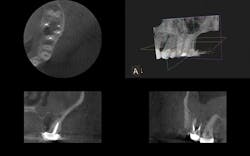

CBCT shows a missed MB2 on the last tooth, the second molar.